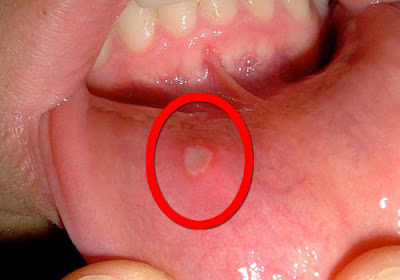

Η άφθα είναι μία επώδυνη επιφανειακή  πληγή στο στόμα. Είναι στρογγυλή ή ελλειψοειδής, διαμέτρου μερικών χιλιοστών. Στον πυθμένα είναι υποκίτρινη και περιβάλλεται από μία κόκκινη άλω.

Εντοπίζεται  στα ούλα, στα χείλη, στις παρειές, στη γλώσσα, στο έδαφος του στόματος και στη μαλακή υπερώα και στο στοματοφάρυγγα.

Οι άφθες ταξινομούνται στις ελάσσονες, διαμέτρου λιγότερο από 10 χιλιοστά που περνάνε σε μία εβδομάδα, στις μείζονες μεγαλύτερες από 10 χιλιοστά που περνάνε σε δύο με τρεις εβδομάδες, και στις ερπητόμορφες, συστάδα πολλών μικρών που προσομοιάζουν με την ερπητοειδή στοματίτιδα.